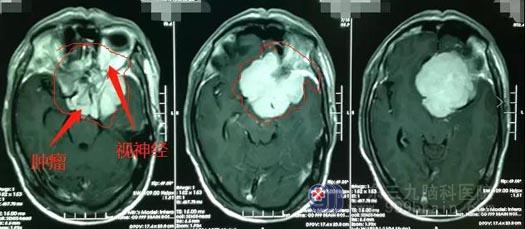

▲菲菲影像检查

我院影像检查显示患儿左侧小脑半球存在占位性病变,大小约为5.4cm*4.1cm*4.0cm。完善相关检查后,鲁明团队为患儿实施了左侧小脑占位病变切除术,手术过程顺利。术后复查MR,患儿颅内的原病灶已被全部切除。